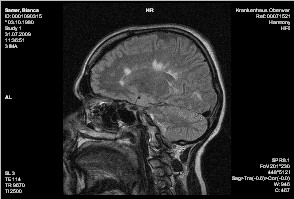

Cerebrum:

Es finden sich multiple, im Balken und periventriculär liegende rund-ovale und fingerförmige T2w hyperintense Glialäsionen, von ihrer Form vereinbar mit Enc. diss. Weiters Glialäsionen um die Hinterhörnder der Seitenventrikel und um das li. Temporalhorn. Die Läsionen zeignen kein Kontrastmittelenhancement.

Keine Ödemzonen. Normal weiter Liquorräume.